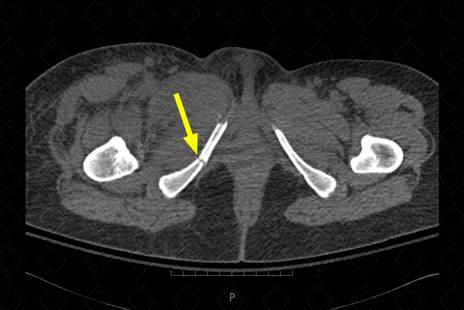

Descrição das figuras 1 e 2: Presença de artefato metálico no ramo ilíaco à direita, compatível com PAF (seta vermelha). Observamos no ramo isquiopubiano, deste lado, traço de fratura associado (seta amarela).